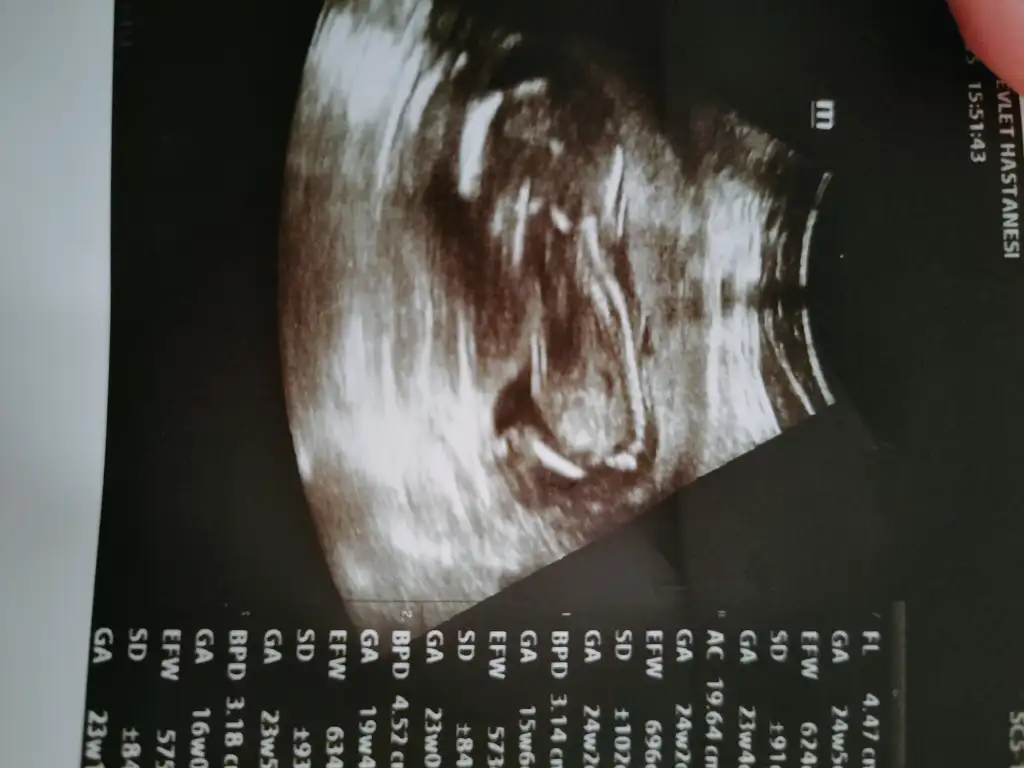

kızlar dun kontrolum vardı :)) oglumuzun bacakları kolları elleri cok guzel olusmus gelisiyor falan dedi... aaaa erkek mi dedim bilmiyor muydun dedi.:110: malum olacak zaar:) amayıne de 20. haftada ne soylersem o olsun sımdıden hazırlık falan yapa dedı:)) bı oglum daha olacak nasipse:)) yanılmadıysa

Oglan dedi de pipiyi gordum demedikten sonra inanmam sahsen ben:)))